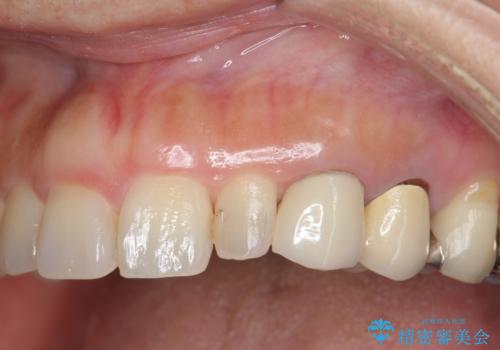

- 左上の前歯が小さく左右対称ではないのと、保険の前歯の被せ物のやりかえを希望して来院。

被せ物だけやりかえており、患者様のご希望もあり、根の治療や土台(コア)のやりかえは行なっていません。

- 25万円 内訳 左上23:ジルコニアクラウン(スペシャル)各10万円、仮歯 各1万円、オフィスホワイトニング(エクセレント)3万円費用は治療当時の料金となります

左右対称に仕上げることができ、治療には非常に満足していただきました。